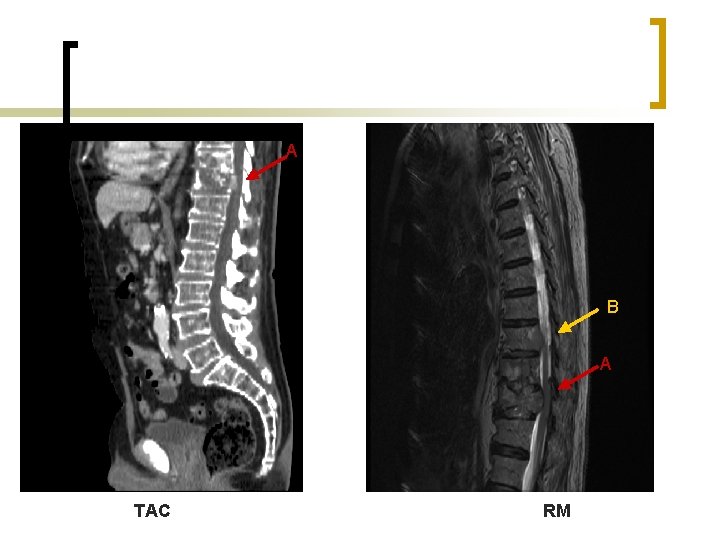

DIAGNÓSTICO RESONANCIA MAGNÉTICA (de elección) n Evaluación exacta de: ¡ localización y extensión de la enfermedad. ¡ afectación de tejido adyacentes y del hueso. n Debe incluir en toda la columna vertebral: 1/3 de los casos afectación múltiple. n Sensibilidad= 93%; Especificidad= 97%. n Aparecen hipointensas en T 1 e hiperintensas en T 2

A B A TAC RM